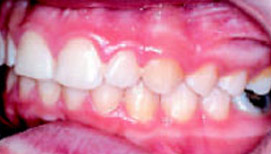

Elasto-Strip

Прозрачная, индивидуально изготовленная по Set-up лента из базисного материала силасто толщиной около двух миллиметров и шириной шесть миллиметров. Приложение силы передается посредством пластиковых кнопок или скобок. Elasto-Strip может применяться у взрослых пациентов с заболеваниями парадонта при протрузии и наличии трем (рис.4).

Позиционеры Elasto-Strip

Elasto-Strip представляет собой прозрачную ленту из Silasto 50 или 70 толщиной примерно 2 мм и шириной 6 мм. Выбор твердости по Шору зависит от величины необходимого перемещения зубов и определяется индивидуально. Elasto-Strip располагается только на вестибулярной поверхности зубов, доставляет меньше неудобств пациенту и поэтому её можно носить и днем дольше, чем другие аппараты Elasto. Лабораторно-технические и клинические этапы такие же, как и при использовании Elasto-Bond.

Показания к применению Elasto-Strip:

- Биальвеолярная протрузия с наличием трем

- Нейтральный прикус с нормальной глубиной перекрытия, с глубоким блокирующим прикусом или открытым в переднем отделе

- Зубоальвеолярная протрузия верхних передних зубов с тремами при нейтральном или дистальном прикусе.

Преимущества изящного Elasto-Strip очевидны для взрослых пациентов (рис.5-8). Он занимает прочное место в качестве основного лечебного аппарата - при определённых показаниях.